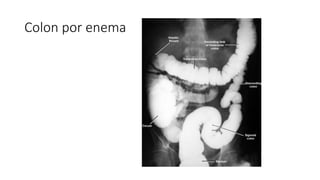

• El estudio radiologico para la valoracion inicial de cualquier patologia

colonica es el colon por enema

Colon por Enema

• Enema simple: sulfato de bario o hidrosoluble

• Para obstucciones, tamaño, contorno, posicion, haustras del colon

• Hidrosoluble para fistula o perforacion

• Doble contraste: sulfato de barrio y aire

• Lesiones planas y pequeñas ulceraciones

Colon por Enema •Enema simple: sulfato de bario o hidrosoluble • Para obstucciones, tamaño, contorno, posicion, haustras del colon • Hidrosoluble para fistula o perforacion • Doble contraste: sulfato de barrio y aire • Lesiones planas y pequeñas ulceraciones